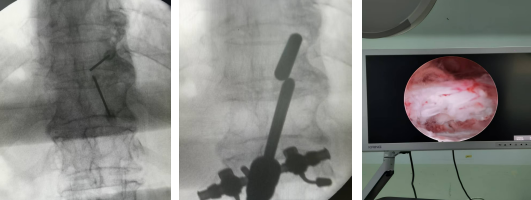

術(shù)中定位、植入U(xiǎn)BE內(nèi)鏡及內(nèi)鏡下減壓完成后脊髓膨隆情況

術(shù)中操作脊柱內(nèi)鏡